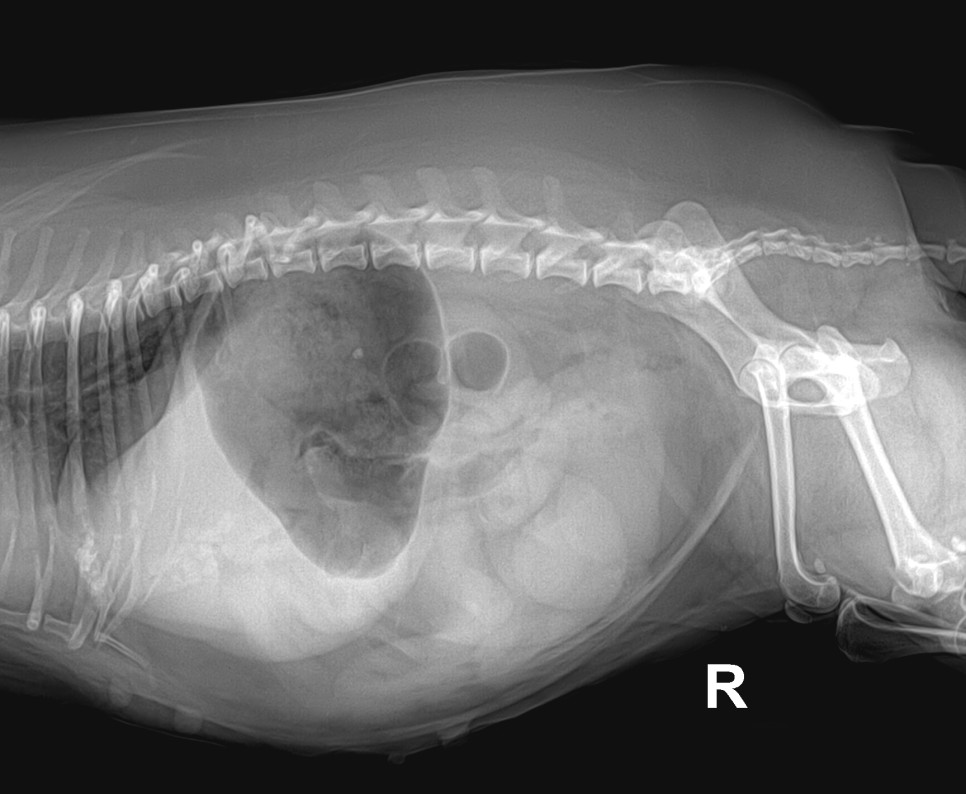

빛나고, 13살 강아지 자궁축농증 송파구 라온펫 동물병원 빛나는 자궁축농증 수술을 위해 내원하였습니다.배가 많이 부른 상태에서 컨디션이 좋지 않아 힘들었기 때문에 긴급하게 수술에 들어가게 되었습니다.

몸집이 작으면서도 팽창하는 듯한 배

자궁축농증 수술 후 거대한 자궁을 꺼내 팽창된 배가 평평하게 들어갔습니다